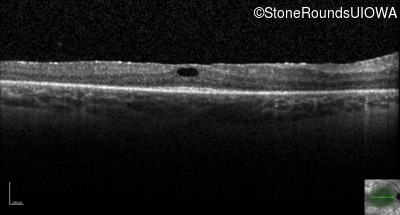

Type 2 Usher Syndrome (IB1b)

Age at visit:

33 years

OD

OS

20/40

20/32 -2

OCT Stack

Diagnosis & molecular findings

Disease

Gene

Allele 1 variant(s)

Allele 2 variant(s)

Inheritance mode

Type 2 Usher Syndrome

USH2A

Cys536Arg TGC>CGC

Trp3521Arg TGG>CGG

AR